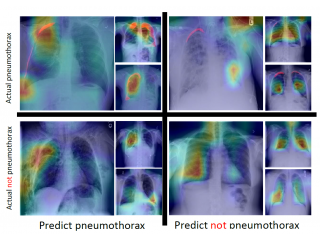

No longer a Black Box––AI Makes Sense, too! –– Discuss Explainable AINo longer a Black Box––AI Makes Sense, too! –– Discuss Explainable AIDeep learning can solve many problems and be used in many tasks, such as image classification, target detection, image segmentation...etc. What does the DL model learn during training? What does it see in the images to base its judgment on? Explainable AI is the answer to such questions.

No longer a Black Box––AI Makes Sense, too! –– Discuss Explainable AINo longer a Black Box––AI Makes Sense, too! –– Discuss Explainable AIDeep learning can solve many problems and be used in many tasks, such as image classification, target detection, image segmentation...etc. What does the DL model learn during training? What does it see in the images to base its judgment on? Explainable AI is the answer to such questions. -